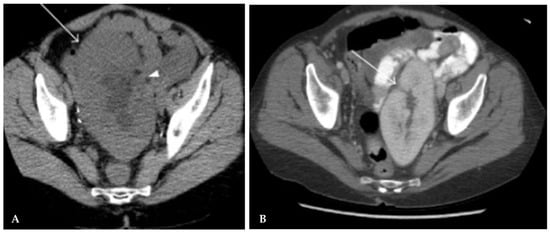

Efficacy of Transcatheter Renal Arterial Embolization to Contract Renal Size and Increase Muscle Mass in Patients with Polycystic Kidney Disease

Background/Objectives: Autosomal dominant polycystic kidney disease (ADPKD) is a major cause of end-stage kidney disease (ESKD), accounting for approximately 5–10% of patients receiving dialysis worldwide. The large and numerous cysts in the liver and kidneys cause abdominal distention and poor appetite. Previous studies showed that renal arterial embolization (RAE) reduces total kidney volume (TKV), increases appetite, and improves quality of life. This article aims to evaluate the efficacy of RAE in increasing psoas muscle (PM) and paraspinal muscle (PS) mass in patients with polycystic kidney disease. Methods: A retrospective study was conducted from May 2016 to December 2020. Thirty-five patients with PKD and ESKD who received RAE were enrolled. The clinical data, including age, sex, body weight, abdominal circumference, and laboratory results, including albumin, creatinine, estimated glomerular filtration rate, and dialysis vintage, were collected. TKV was calculated with the ellipsoid formula method, and muscle mass was measured with bilateral PM and PS areas at the third lumbar level. The associated clinical, laboratory, and imaging data were compared before and after RAE. Results: There were 19 females and 16 males with a mean age of 59.9 for the final analysis. There were significant changes between baseline and 3-month, 6-month, 12-month after RAE, such as a decrease in TKV (4684 ± 3361 vs. 4079 ± 3456, 3675 ± 3401, 2459 ± 1706 mL, all p < 0.001), an increase in the PM area (12.6 ± 5.8 vs. 13.3 ± 5.7, 14.7 ± 6.9, 14.3 ± 7.1 cm2, all p < 0.05), but no difference in body weight, body mass index, albumin, hemoglobin, creatinine, or estimated glomerular filtration rate. The increase in the PM and PS was more obvious in the sarcopenic group than in the non-sarcopenic group in the 12-month follow-up (p = 0.001 and 0.016 vs. p = 0.205 and 0.259). Conclusions: RAE effectively reduces TKV, increases PM and PS mass, and serves as a candidate to reverse muscle loss in patients with PKD. Full article

(This article belongs to the Section Medical Imaging and Theranostics)

Show Figures

Figure 1